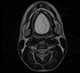

Midline dermoid

Dermoid sinus is a thought to be a genetic skin condition in dogs. It is also known as pilonidal sinus. [Source: Wikipedia ]